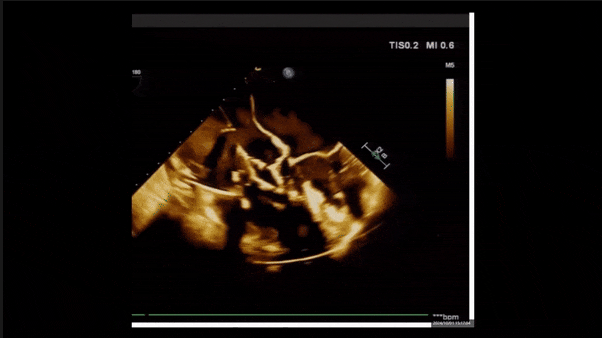

術(shù)前TEE評估

1、3D TEE顯示雙房及右室擴大,右室中段直徑40mm,右室FCA 52%。三尖瓣環(huán)TAPSE 22mm,三尖瓣環(huán)左右徑49mm,三尖瓣隔葉長度16mm,前葉長度21mm,后葉長度34mm,三尖瓣前隔gap 11mm,后隔gap 5.6mm,AP gap 12mm,診斷極重度功能性三尖瓣返流(Type I型三尖瓣:Torrential FTR 5+)。

2、彩色多普勒顯示:收縮期三尖瓣口返流束起源于后隔交界、前后葉之間及前隔交界,返流束縮流頸最大寬度27mm,三尖瓣返流口EOA=2.02cm2,返流容積124ml,收縮期三尖瓣返流峰值速度2.64m/s,返流峰值壓差28mmHg,PAPs 43mmHg,舒張期三尖瓣口平均跨瓣壓差1mmHg,肝左靜脈可見明顯逆向血流波。

術(shù)后即刻返流三維

術(shù)中經(jīng)食道超聲輔助下可見LuX-Valve Plus夾持件抓捕瓣葉狀態(tài)良好,夾持件在位,室間隔錨定位置良好,假體瓣膜整體錨定狀態(tài)穩(wěn)固。

術(shù)后三維超聲

術(shù)后即刻經(jīng)食道超聲可見,三尖瓣假體瓣膜位置合適,牛心包瓣葉運動狀態(tài)良好,開閉正常,瓣周及瓣葉對合緣處未見明顯返流,心電圖及心包狀態(tài)較術(shù)前無明顯變化。